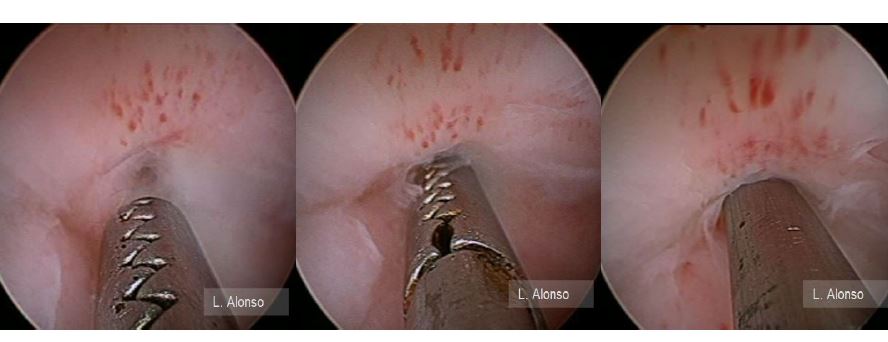

Dr. Luis Alonso Pacheco The hysteroscopic surgical isthmocele correction technique consists of four steps following Gubbini’s recommendation. As previously mentioned,Continue Reading